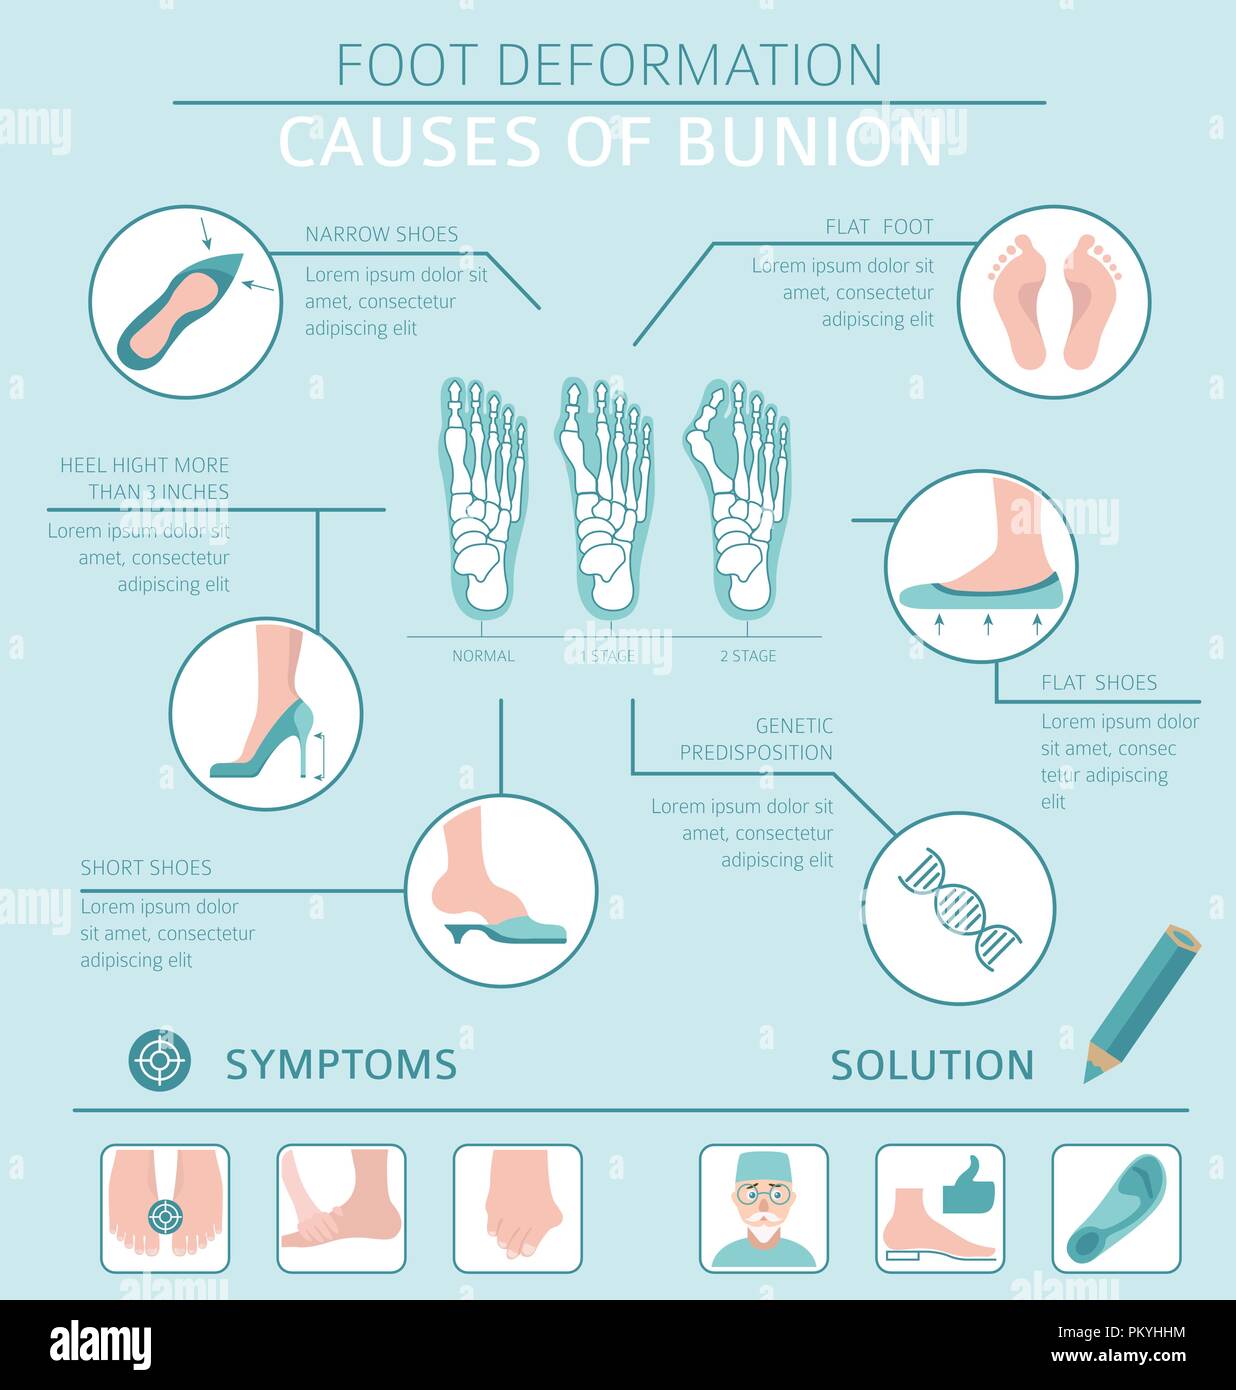

RFPKYHHM–La déformation du pied en tant que maladie médicale infographie. Causes de l'oignon. Vector illustration

RFPKYHRK–La déformation du pied en tant que maladie médicale infographie. Causes de l'oignon. Vector illustration